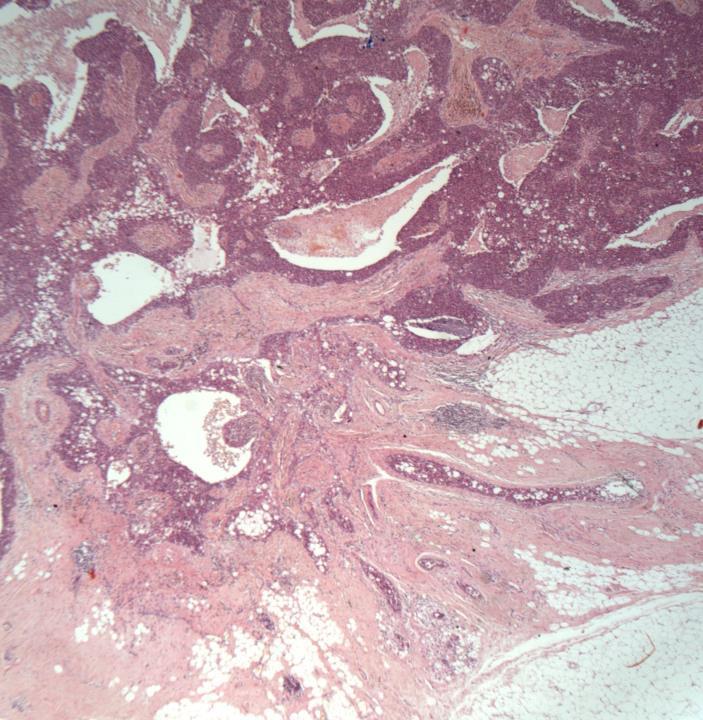

◼ Invasive no special type (NST) carcinoma with basal like features.

◼ Lymphovascular invasion

Morphological features of basal tumours

◼ Pushing margin

◼ Central scarring/necrosis

◼ Syncytial growth pattern

◼ Prominent lymphocytic infiltrate

◼ Metaplastic carcinoma, grade 3

DCIS

Current WHO Classification for Metaplastic ca

◼ Squamous cell carcinoma

◼ Spindle cell carcinoma

◼ Carcinoma with mesenchymal differentiation

◼ Low grade adenosquamous ca

◼ Fibromatosis like ca

◼ Mixed

All have a basal phenotype